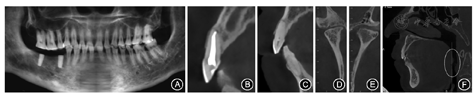

锥形束CT示45、47牙位种植体影像(图2A);11已行根管治疗,根充恰填(图2B),12未行根管治疗(图2C),11、12根尖区及余牙未见明显异常;双侧髁突骨结构改变,不对称,关节前间隙增宽,髁突在关节窝后位(图2D,图2E),锥形束CT显示患者气道中部存在狭窄(图2F)。